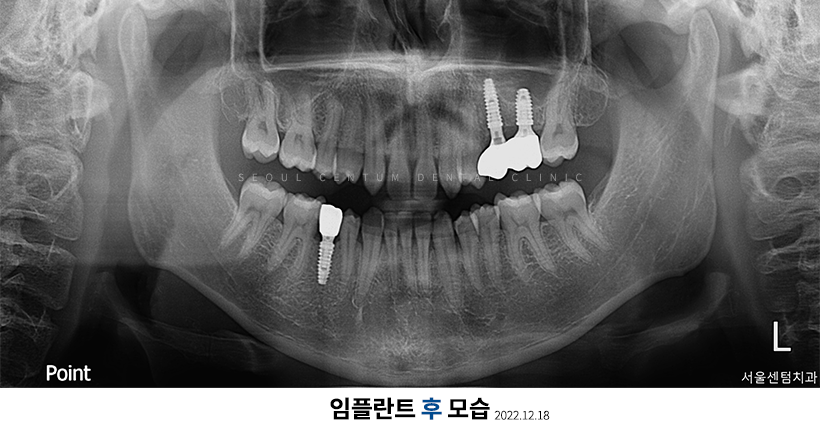

실제로 저희 치과에 내원해 주신 한 환자분의 파노라마 엑스레이 사진입니다.

임플란트2차수술과정은 먼저 잇몸을 개방하고 픽스처를 체결한 위치에 어버트먼트를 연결해 보철물을 장착할 수 있도록 다시 봉합시키고 치아본을 뜹니다. 그리고 약 2주 뒤에 지르코니아 같은 보철물을 장착하는 것이 되겠습니다. 임플란트2차수술과정은 1차에 비해 난도가 낮기 때문에 수술 시간이 10~20분으로 짧고 통증이나 출혈도 덜합니다.

임플란트 1차 / 2차 수술 기간

임플란트를 1차만 하면 23개월 정도가 소요되는 편이지만 2차 임플란트까지 진행하는 경우에는 1차 수술 후 골융합이 충분히 이뤄질 수 있는 기간(약 23개월)이 경과 후 진행합니다. 그래서 1차와 2차 임플란트 수술을 해야 한다면 총 3~6개월 정도가 소요되며 뼈이식을 많이 진행하거나 골융합 속도가 더딘 등의 이유로 기간이 더 길어질 수도 있습니다.